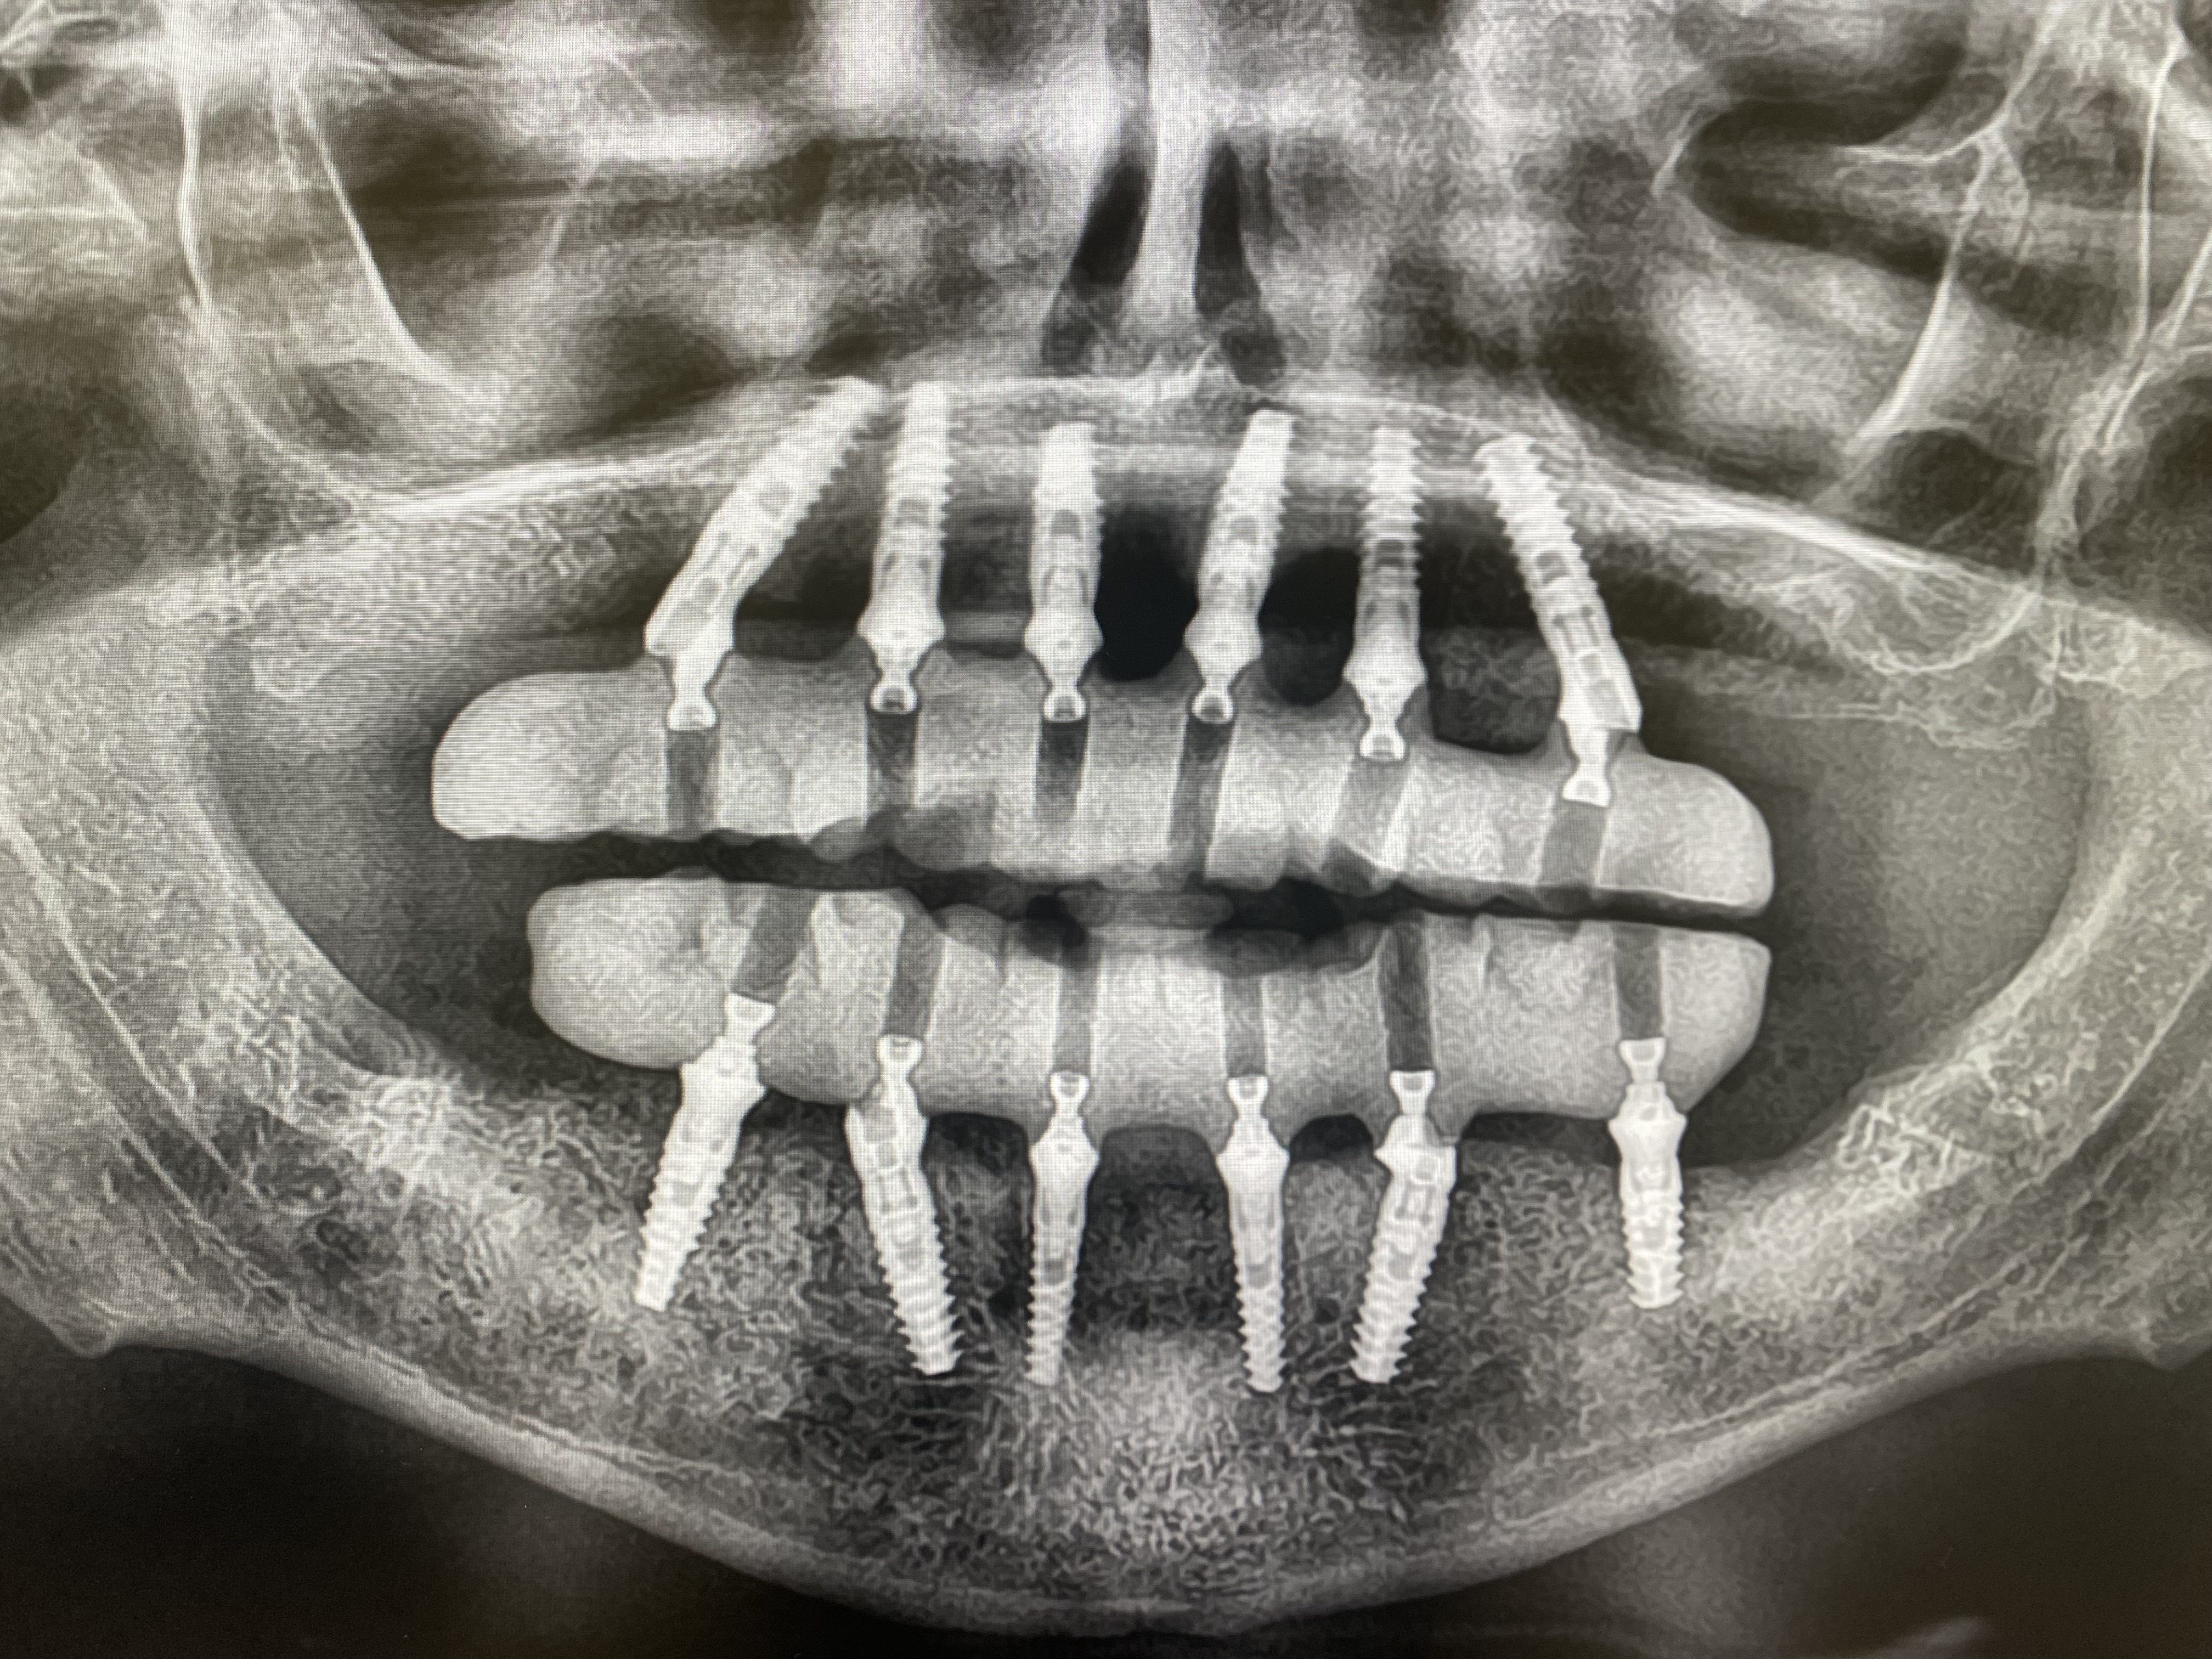

Transforming your smile is a significant decision that deserves expert guidance. Dr. Bitchatchi will evaluate your case, discuss your goals, and create a personalized treatment roadmap designed for your unique needs.